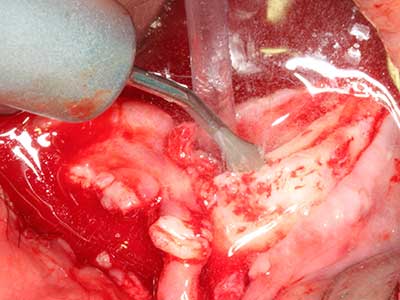

Когато се извършват хирургични процедури върху кост в непосредствена близост до чувствителни структури като кръвоносни съдове или нерви, ротиращите инструменти създават значителен риск за ятрогенно нараняване. Пиезоелектрическите апарати могат да бъдат от помощ при препарация на костно покритие и отстраняване на твърда кост близо до нерви, особено за оголване на нервите след ятрогенно нараняване, както и по време на латерализация на нервите за резекционни и реконструктивни процедури или поставяне на имплант (Фиг. 17-20). Лекият контакт между пиезонакрайника и нерва по принцип не води до нараняване, но ако действате непредпазливо с трионообразни движения или приставки за остатъчен костен субстрат, може да причините временно или перманентно увреждане на нерва. Въпреки това, рискът от увреждане се счита за много по-малък, отколкото при употреба на триони или ротиращи инструменти (Pereira, Gealh et al. 2014).